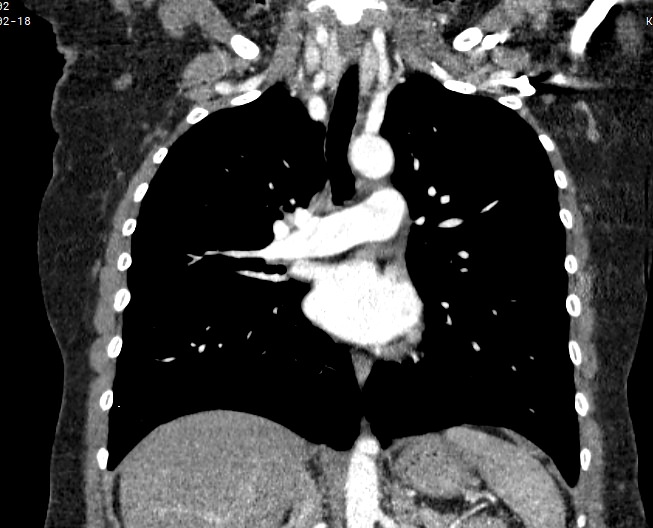

Мультиспиральная компьютерная томография – это современный высокоинформативный рентгенологический метод диагностики различной патологии легких. КТ основана на применении рентгеновского излучения. Однако в отличие от обычного рентгена, при котором снимки делаются в одной плоскости и изображения органов могут накладываться друг на друга, КТ лишена этих недостатков, так как во время компьютерной томографии сканирование проводится в различных плоскостях.

Во время исследования рентгеновская трубка томографа вращается вокруг исследуемой области и производит множество послойных снимков с шагом 0,5-1 мм. Полученные снимки поперечного сечения с помощью компьютерной программы могут быть преобразованы в 3D-изображения исследуемого органа или участка ткани. Это позволяет выявлять практически все заболевания легких на ранних стадиях и назначать своевременное лечение.

В некоторых случаях, например, при подозрении на опухолевый процесс, проводится КТ легких с контрастированием, когда для лучшей визуализации патологического очага пациенту внутривенно вводится йодсодержащий контрастный препарат. Контрастное вещество накапливается в патологических участках и обеспечивает их яркую визуализацию на фоне неизмененной ткани. С помощью контрастирования можно визуализировать кровеносные сосуды, выявить первичные опухоли и метастазы в легких, дифференцировать новообразования, например, отличить доброкачественную опухоль от злокачественной.

В медицинском центре «Доступная медицина» установлено современное оборудование – 64-срезовый и 128-срезовый компьютерные томографы TOSHIBA AQUILION, на которых проводится сканирование легочной ткани. За счет увеличенного количества детекторов аппараты производят снимки с большой скоростью и минимальной дозой облучения. При этом инновационные цифровые приложения позволяют получить объемные изображения легочной ткани высокой четкости, контрастности и в мельчайших подробностях.